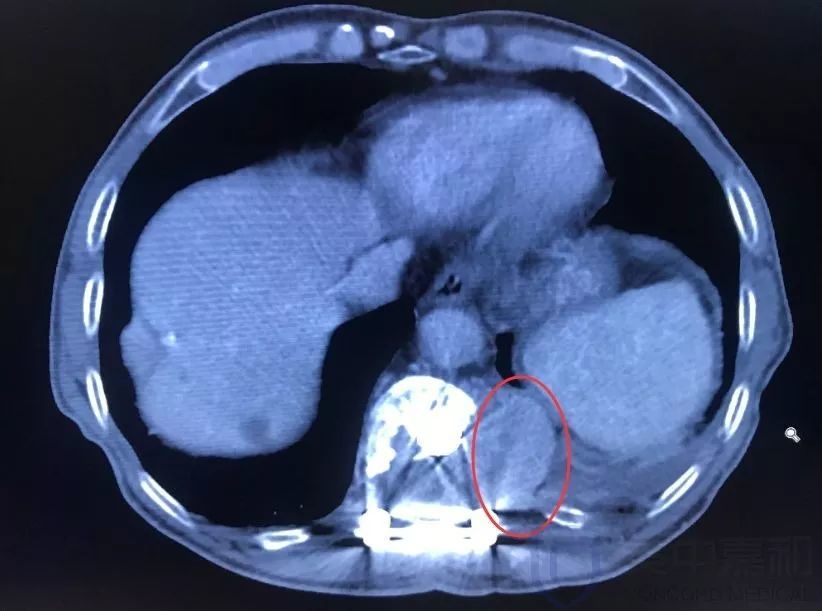

骨转移ct

肺癌骨转移ct图片